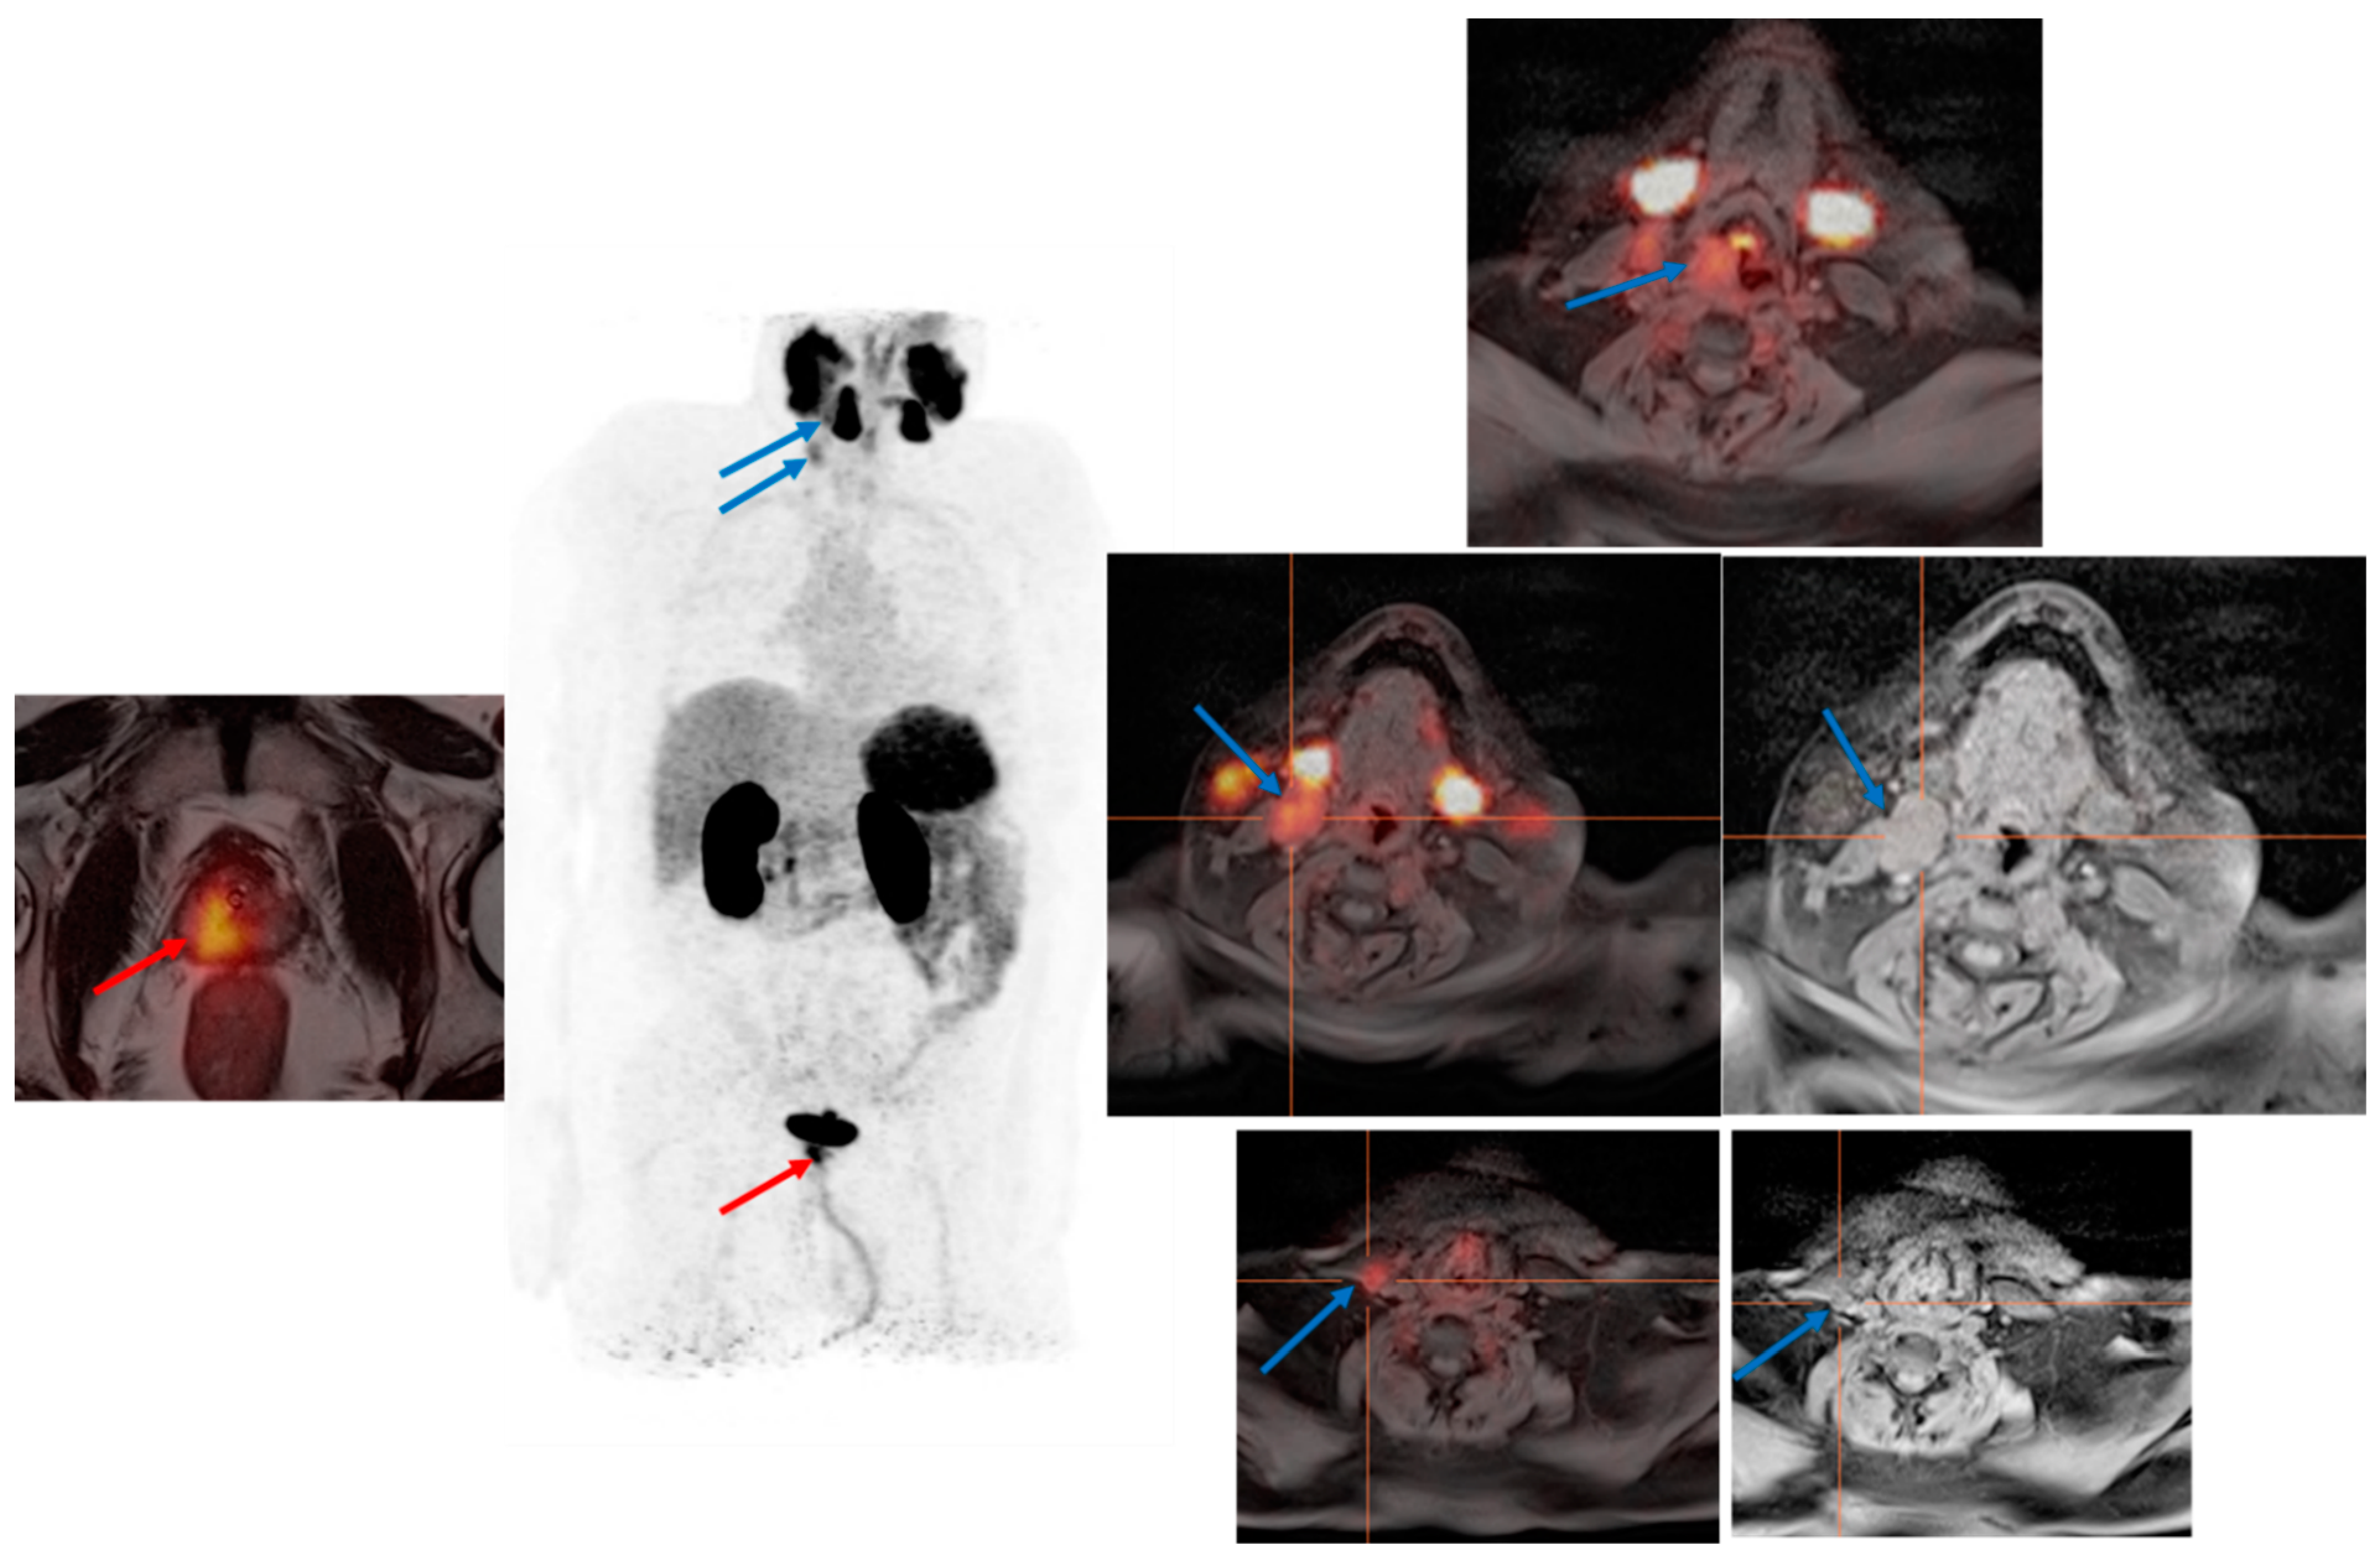

3.3. Evaluation of PCa Patients for Possibility of PSMA Radioligand Therapies

4. Pitfalls and Limitation of PSMA PET Examination